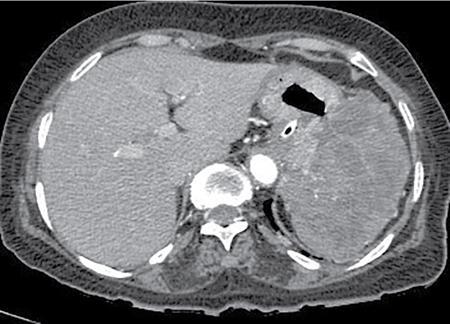

A 60-year-old male with history of chronic alcohol consumption and chronic weight loss and pain epigastrium presented to Radiology for USG. A finding on USG called for a barium meal and follow-through for academic purpose.

Key findings

Barium meal and follow-through spot image revealed widening of C loop of duodenum along with extrinsic compression on the antrum posteroinferiorly giving rise to classical ‘antrum pad’ sign. There was, however, no obvious mucosal irregularity seen. There is evidence of contrast hold-up.

Analysis and interpretation

The image showcases two classical signs in GI radiology which are the ‘widening of C loop of duodenum’ and the ‘antral pad sign’. Both the signs are typically described in masses of head of pancreas. A comment on the mucosal lining (regular/irregular) may give a pointer towards the mass being malignant. However, this is a nonspecific sign giving indication of a mass effect and has a variety of differentials. The final diagnosis is reached with the help of cross-sectional imaging and/or endoscopy/biopsy. CECT abdomen in this case confirmed it to be a case of carcinoma pancreas (Fig. 7.4.6.1).

Image

Fig. 7.4.6.1 CECT showing a mass in the head of pancreas.

Carcinoma head of pancreas

• a) Widening of C loop with irregular mucosal margins.

• b) Antral pad sign.

• c) Frostberg inverted 3 sign.

• d) Definitive diagnosis with CECT.

Fig. 7.4.6.2 Barium meal depicting widened C loop of duodenum.